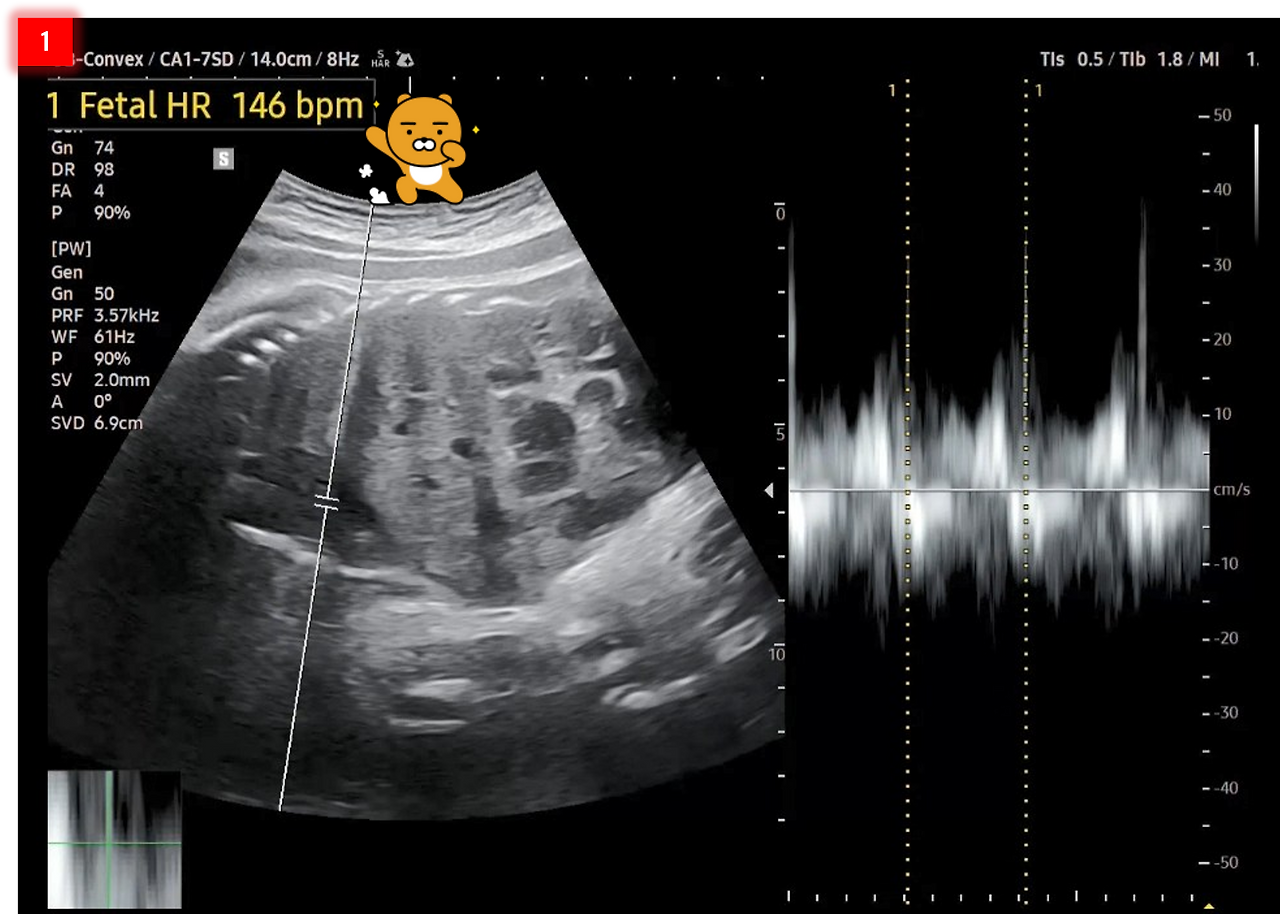

2. 태아 머리직경(BPD: Biparietal Diameter)은 8.08㎝이고, 태아 복부 둘레(AC: Abdominal Circumference)는 29.54㎝이네요. 머리직경이 평균(8.5~9㎝)보다 좀 작은 편이고, 복부둘레는 평균(27.5~30㎝)에 드네요.

BPD&AC.png [태아 머리직경과 복부 둘레]